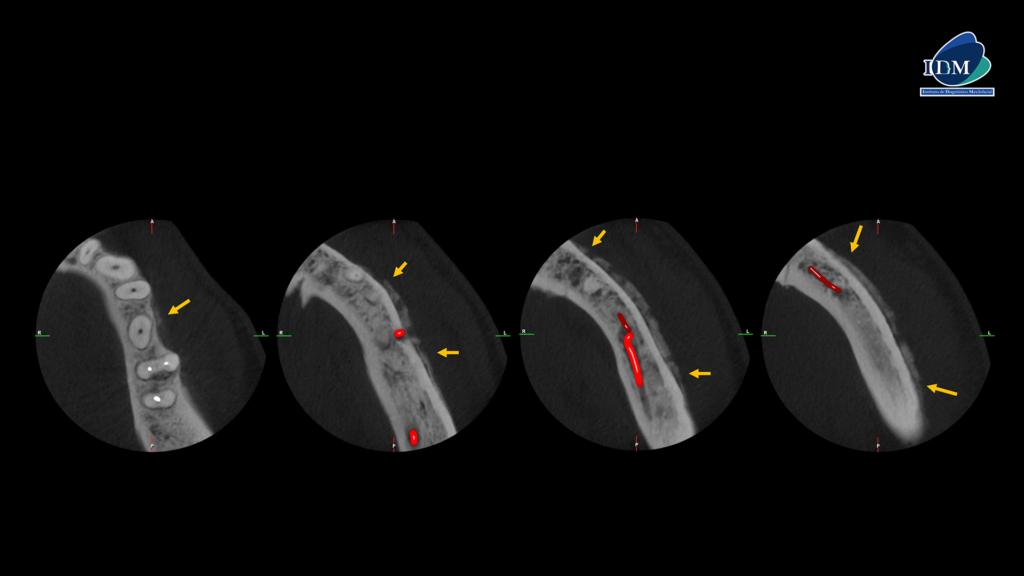

En el estudio complementario mediante tomografía computarizada de haz cónico (TCHC), se confirma la presencia de una reacción ósea perióstica que afecta la tabla ósea vestibular, la basal mandibular y, parcialmente, la tabla ósea lingual en su región caudal (cortes axiales, tangenciales y transaxiales). En las piezas dentarias, se observa una obturación parcial de los conductos y procesos osteolíticos periapicales en la pieza 36 (cortes transaxiales).

CORTES AXIALES